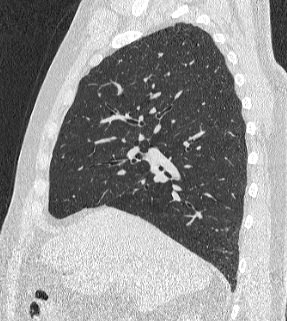

Во время исследования рентгеновская трубка томографа вращается вокруг исследуемой области и производит множество послойных снимков с шагом 0,5-1 мм. Полученные снимки поперечного сечения с помощью компьютерной программы могут быть преобразованы в 3D-изображения исследуемого органа или участка ткани. Это позволяет выявлять практически все заболевания легких на ранних стадиях и назначать своевременное лечение.

В медицинском центре «Доступная медицина» используется современный 128-срезовый компьютерный томограф TOSHIBA AQUILION CXL, на котором проводится сканирование легочной ткани. За счет увеличенного количества детекторов аппарат производит снимки с большой скоростью и минимальной дозой облучения. При этом инновационные цифровые приложения позволяют получить объемные изображения легочной ткани высокой четкости, контрастности и в мельчайших подробностях.